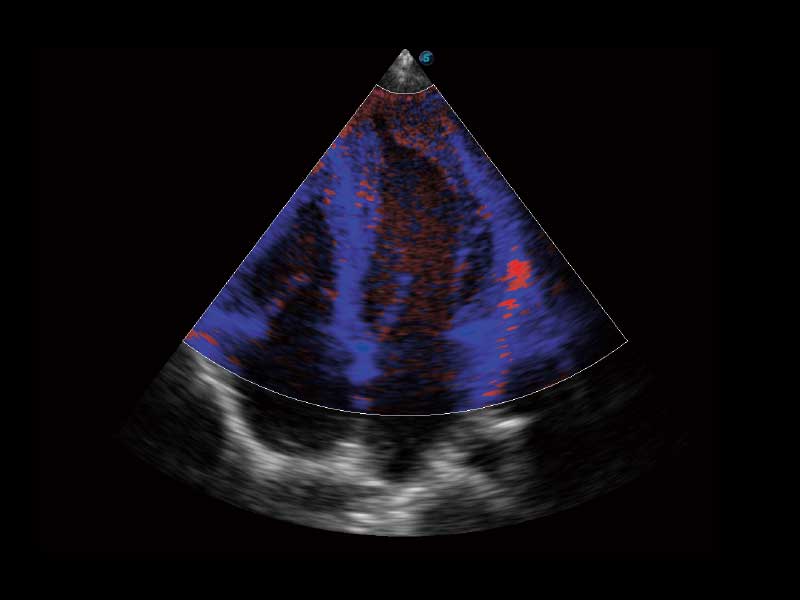

μ-Scan微米成像、空间复合成像、高分辨率血流成像。